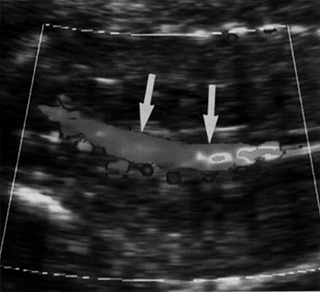

Υπερηχογραφικά, η κατάσταση αυτή γίνεται αντιληπτή με πλήρη απουσία αμνιακού

υγρού και μη ορατή ουροδόχο κύστη. Το έγχρωμο Doppler βοηθά στη διάγνωση -δεν

απεικονίζονται οι νεφρικές αρτηρίες και επιβεβαιώνεται η απουσία νεφρών (εικόνες

2, 3).

| Εικόνα 1. Φυσιολογική απεικόνιση των νεφρών. | Εικόνα 2. Φυσιολογική

απεικόνιση νεφρικών αρτηριών. |

Εικόνα 3. Απουσία νεφρικών αρτηριών. |